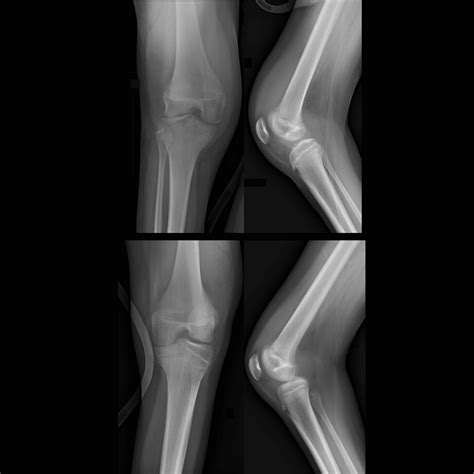

Joint effusion occurs when excess fluid accumulates in the joint space, leading to swelling and discomfort. This condition can affect any joint in the body, but it is most commonly observed in the knees, elbows, and ankles. The fluid buildup can be due to various factors, including injury, infection, or underlying medical conditions.

• Imaging Tests: X-rays, MRI, or ultrasound may be used to visualize the joint and assess the extent of fluid buildup.